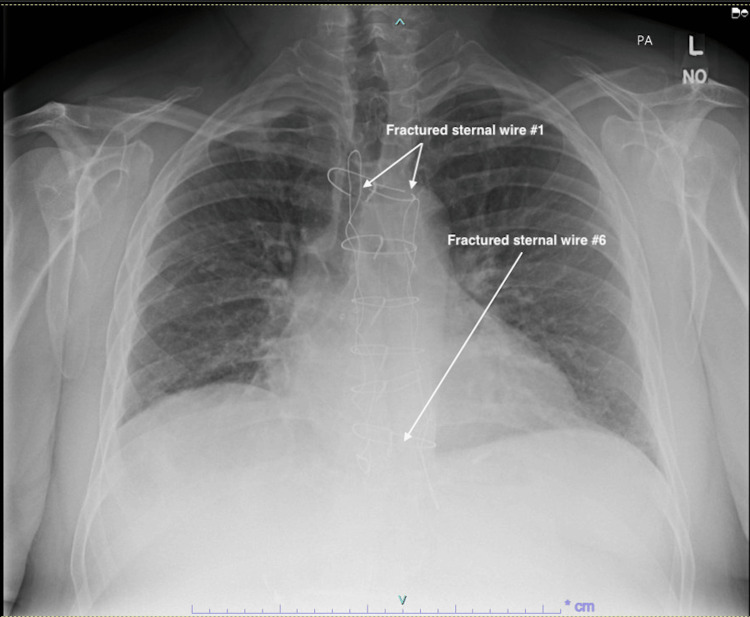

Before assessment in our outpatient clinic, the patient underwent a chest X-ray, as well as CT and echocardiography imaging for structural and functional evaluation. X-ray and CT chest imaging (Figures 1–2) revealed probable chronic non-union of the sternum with no evidence of dense bony bridging across the sternum. There was no evidence of any acute or concerning abnormalities in the anterior mediastinum or definite acute abnormalities in the chest. The imaging also showed that wires number one (Figure 2A) and six (Figure 2B) were broken.

Video 1 shows a transverse view of the chest CT imaging, demonstrating the full-length chronic sternal non-union, as well as the fractured wires one and six.